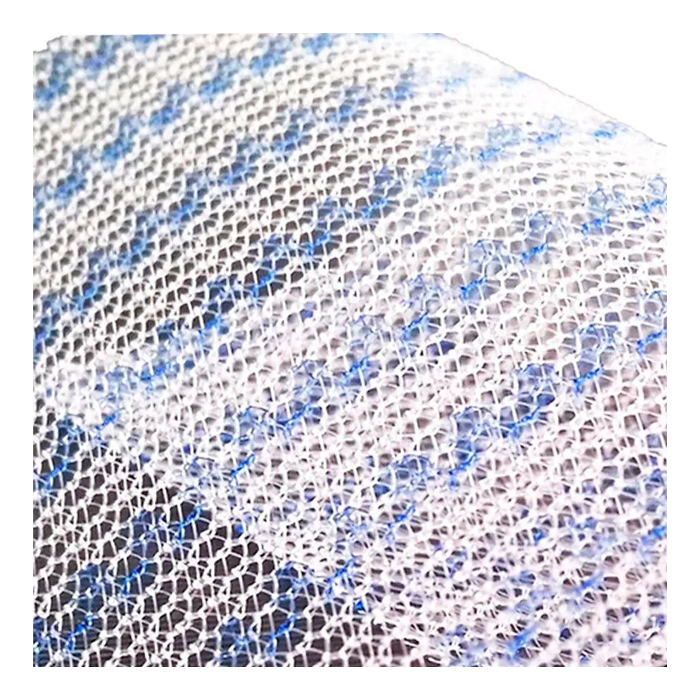

Эндопротез-сетка (сетка хирургическая) полипропиленовый для восстановительной хирургии ЭСФИЛ лёгкий, 30х10 см, Линтекс

Эндопротез-сетка полипропиленовая ЭСФИЛ лёгкий для восстановительной хирургии

Эндопротез-сетка ЭСФИЛ лёгкий от компании «Линтекс» — это современный полипропиленовый имплантат, разработанный для эффективного и надежного восстановления анатомических структур в хирургической практике. Изделие размером 30х10 см представляет собой легкую макропористую сетку, которая служит прочным каркасом для укрепления тканей и стимулирования их естественной регенерации.

Ключевое преимущество сетки ЭСФИЛ лёгкий — её особая конструкция, обеспечивающая высокую биосовместимость и минимальную реакцию со стороны организма. Это позволяет снизить риск послеоперационных осложнений и способствует быстрому восстановлению пациента.

- Минимальная реакция тканей: Макропористая структура и легкий вес материала способствуют быстрому прорастанию соединительной ткани, формируя прочный рубцово-сетчатый комплекс с минимальным риском образования грубых спаек.

- Удобство в работе: Материал легко моделируется и кроится непосредственно в операционной, идеально адаптируясь к анатомическим особенностям пациента. Сетка не скручивается и хорошо держит заданную форму.

| Тип структуры | Макропористая, легкая, не расслаивающаяся |